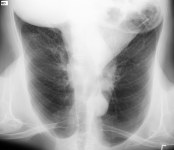

也可以从下拉菜单中应用旋转和翻转操作。

可以对图像叠加应用多次旋转和翻转,以获得所需方向。

选择 清除变换(或按 Ctrl + Shift + \)可恢复原始方向。